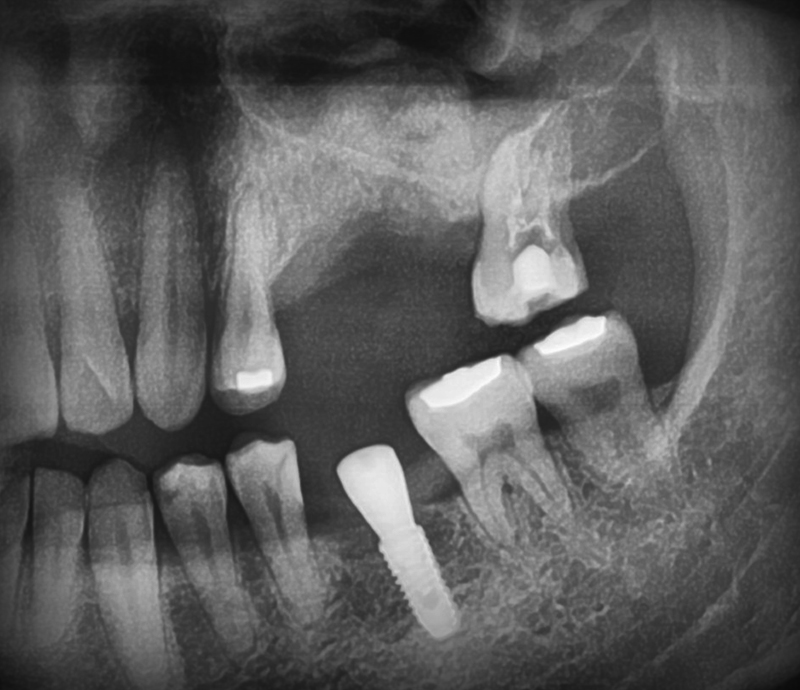

20번대 수술 후 CT

구치부는 6.4mm 직경에 5.6mm 길이의 뼈가 남아있고, 소구치부는 6.5mm 정도의 뼈가 남아있는 상태였습니다. 20번대 수술하면서 상악동 내부 인공 치조골 이식을 동반 실시하였습니다.

10번대 구치부 상악동 수술 필요

2.9mm 남은 상악 우측 대구치부를 확인해보니 상악 우측 어금니 부위 뼈의 두께는 2.9mm입니다. 발치한지 오랜 시간이 지났고 뒤에 지지하는 치아도 없기 때문에 후방연장 틀니를 사용하면서 계속적인 교합력이 치조골에 가해졌고 점차 잇몸뼈 흡수가 가속화 돼서 2.9mm 밖에 남지 않았습니다. 임플란트를 심기 위해 8mm 정도의 두께의 뼈가 있는 것이 좋으나 지금처럼 원하는 뼈의 25% 밖에 없는 경우는 *상악동의 옆 창문을 열고 인공 치조골 이식을 동반하여 치료를 하는 것이 좋습니다. 측방접근법 상악동거상술  이 경우 술 후 5~6개월의 숙성과정을 거쳐 뼈가 잘 형성된 것을 확인하고 보철을 만들게 됩니다.

20번대 소구치부 CT

발치한 뒤 오랜 시간이 지나면 치조골이 흡수되어 없어집니다. 특히 바깥 부분이 빠르게 없어지는 것은 20번대 고수치부CT에서 확인할 수 있었습니다. 이 부위는 폭이 5.2mm밖에 남아있지 않아 3.5mm 정도 또는 인공 치조골을 이식하여 4.0mm 정도의 임플란트를 식립할 수 있었습니다. 소실된 우측 송곳니와 소구치 사이에서 두꺼운 치조골 부위는 찾아 의도적으로 방향을 꺾어 임플란트를 식립하기로 계획하였으며 사진은 수술 후 6개월 뒤 보철을 올려 마무리된 파노라마입니다.